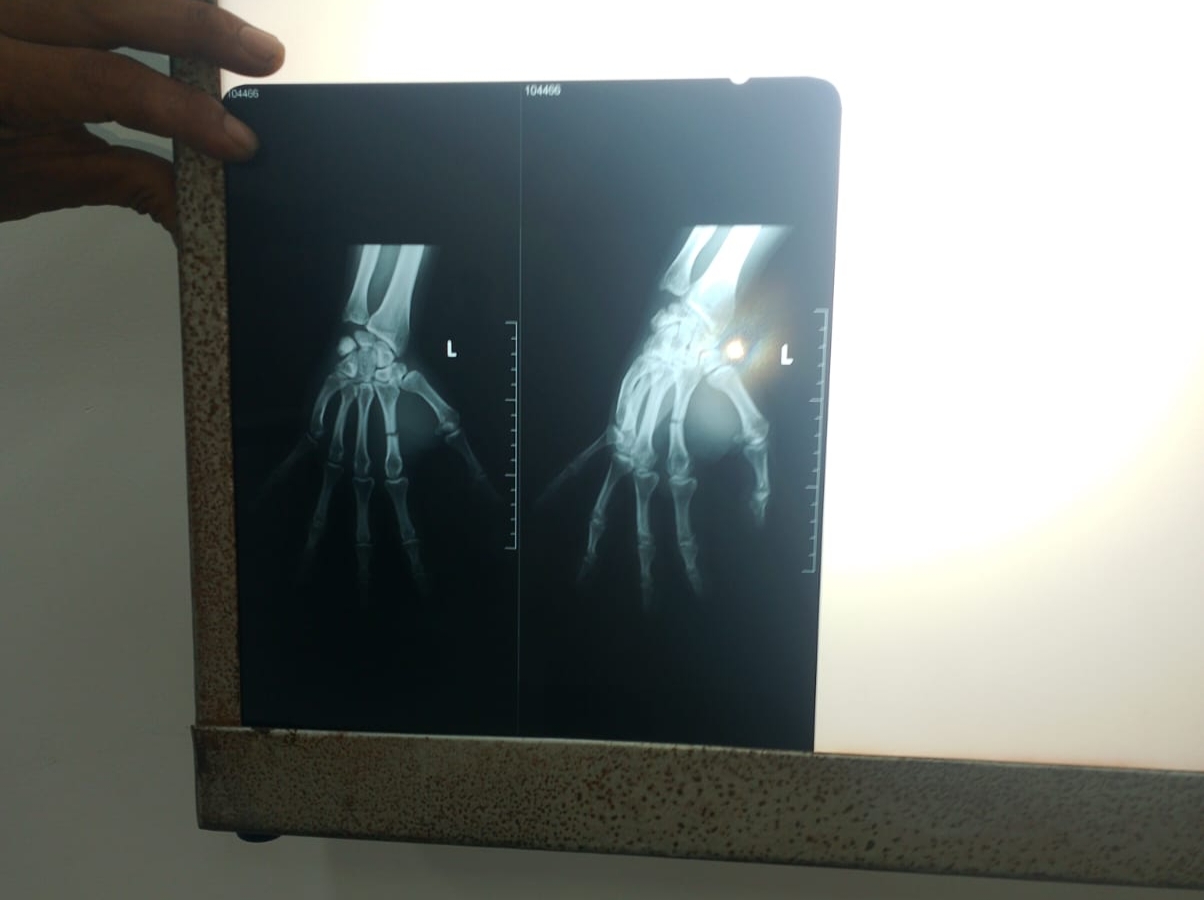

Saat itu korban mencoba melerai dua Pemuda yang sedang terjadi keributan di depan wahana Rumah Hantu, tiba-tiba datang pelaku (AN) membawa sebatang besi panjang dan memukul tangan kanan korban hingga menyebabkan luka robek dan patah tulang pada bagian jari telunjuk Korban.

Korban dilarikan ke RSUD Bayung Lencir untuk dilakukan pertolongan pertama. Kemudian melaporkan kejadian tersebut ke Polsek Bayung Lencir, dilakukan visum dan dimintai keterangan oleh polsek Bayung Lencir bersama dengan beberapa saksi kejadian.